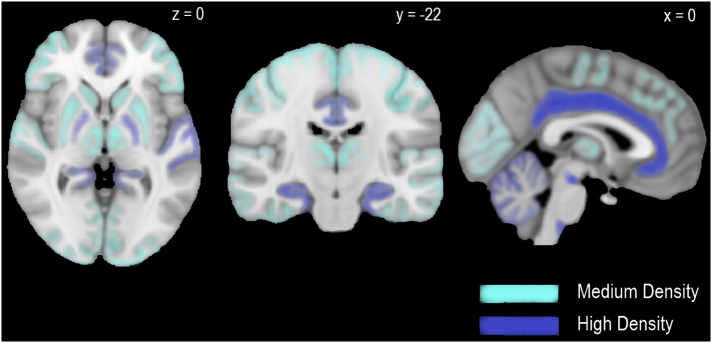

The main psychoactive substance in cannabis is Δ9-tetrahydrocannabinol (THC) (ref. Wachtel et al., 2002) which was first isolated from hashish in 1964 by Gaoni and Mechloulam. THC is gaining interest for its broad therapeutic potential. This includes putative anti-epileptic properties (ref. Friedman & Devinsky, 2015), analgesic properties in neuropathic and chronic pain (ref. Abrams et al., 2007; ref. Mucke et al., 2018; ref. Narang et al., 2008; ref. Svendsen et al., 2004; ref. Wilsey et al., 2008), anti-emetic properties in cancer (ref. Davis, 2016; ref. Smith, Azariah, et al., 2015), and anti-spastic properties in stroke and multiple sclerosis (ref. Collin et al., 2007; ref. Marinelli et al., 2017). THC was originally described as an agonist of endocannabinoid CB1 receptors (CB1R) (ref. Felder et al. 1992), however, there is growing evidence of partial agonist properties at this site from both in vitro (ref. Breivogel & Childers, 2000; ref. Govaerts et al., 2004; ref. Kelley & Thayer, 2004; ref. Petitet et al., 1998; ref. Shen & Thayer, 1999; ref. Sim et al., 1996) and in vivo (ref. Paronis et al., 2012) studies. The CB1R is a widespread G protein-coupled receptor (ref. Pertwee, 2008) found at high concentrations in key brain regions associated with reward, emotional and cognitive processing including the neocortex (particularly frontal and limbic areas), hippocampus, amygdala, cerebellum, thalamus and basal ganglia (see Fig. 1) (ref. Glass et al., 1997). THC alters signalling of endocannabinoid transmitters such as 2-arachidonoylglycerol and anandamide. These ligands are released endogenously by neurons and act on CB1Rs in adjacent γ-aminobutyric acid (GABA)-ergic and glutamatergic nerve terminals resulting in retrograde signalling (see Fig. 2) (ref. Bloomfield et al., 2016; ref. Castillo et al., 2012). THC also demonstrates partial agonist properties in vitro at the CB2 receptor, but with lower efficacy than at CB1R. (ref. Pertwee, 2008). As THC has a number of double bonds and stereoisomers, this review focuses on the main THC isomer found in cannabis, (−)-trans-Δ9-tetrahydrocannabinol, which is also referred to in some older studies by its alternative name Δ1-tetrahydrocannabinol and as a pharmaceutical preparation using the International Non-Proprietary Name dronabinol.